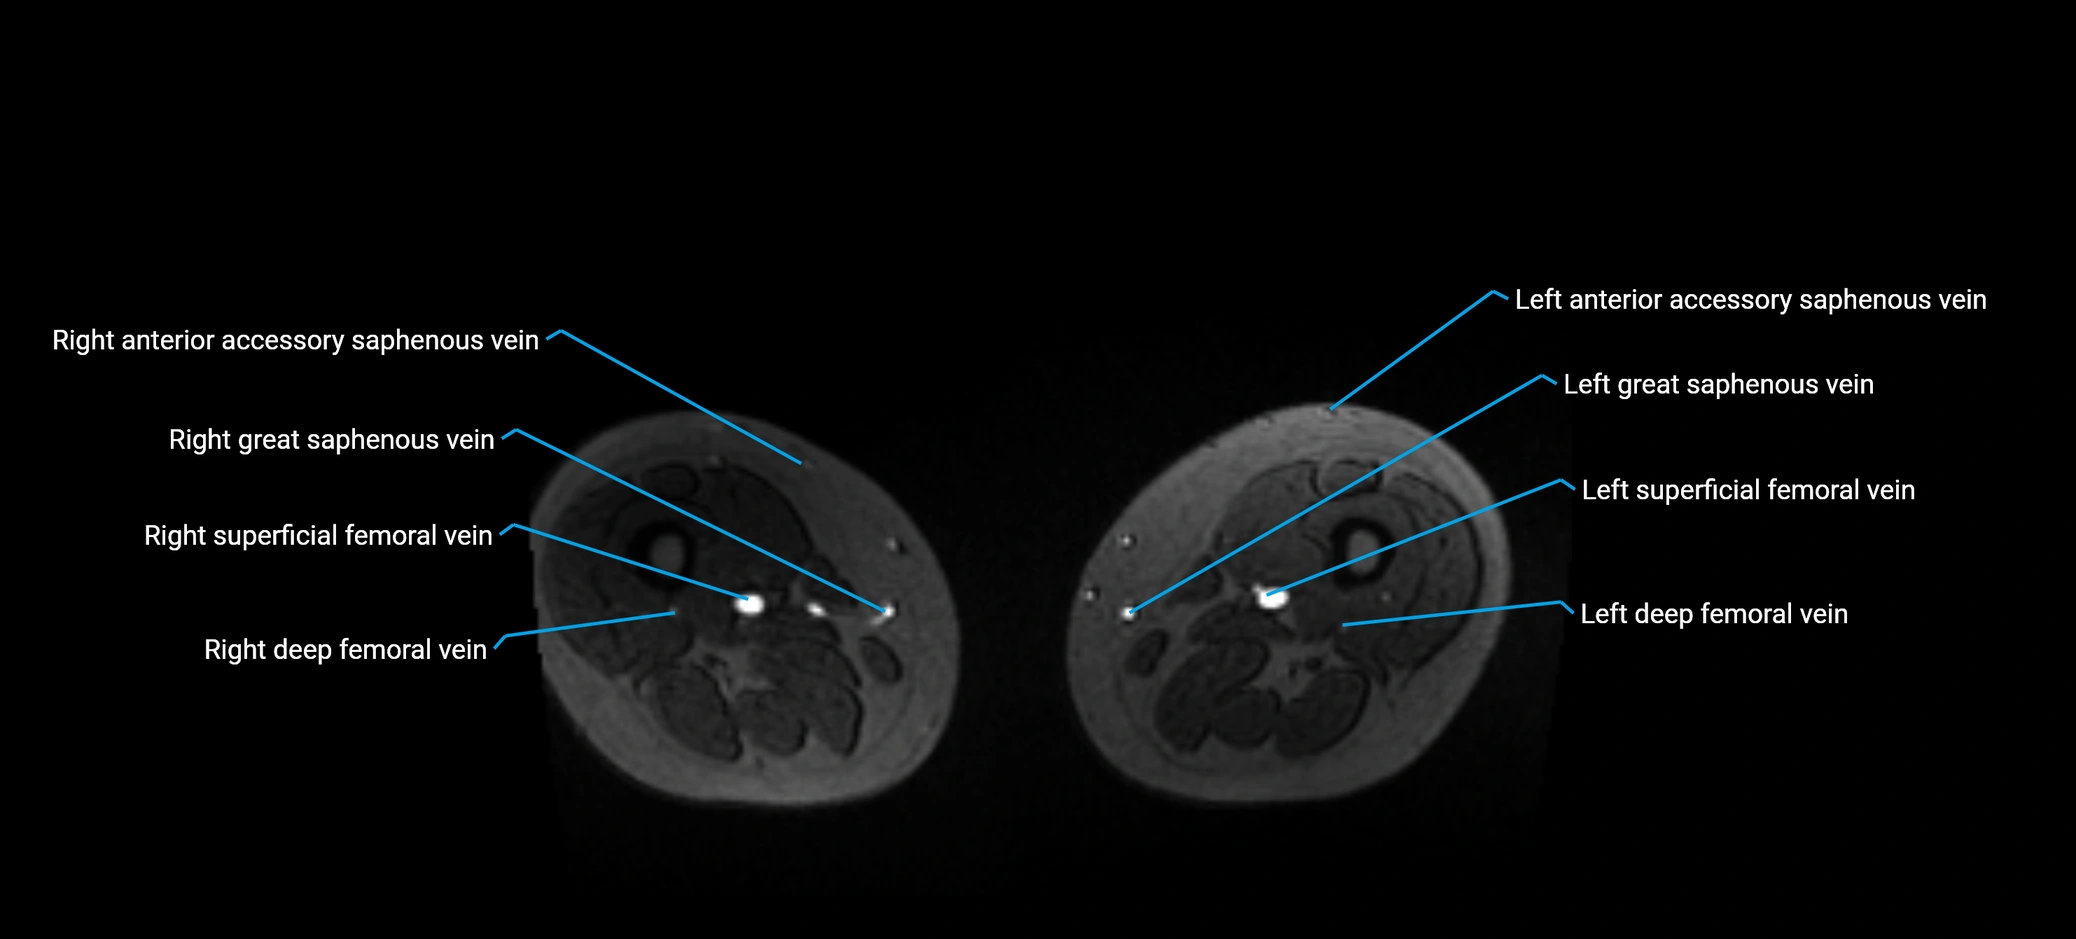

MRI image

image